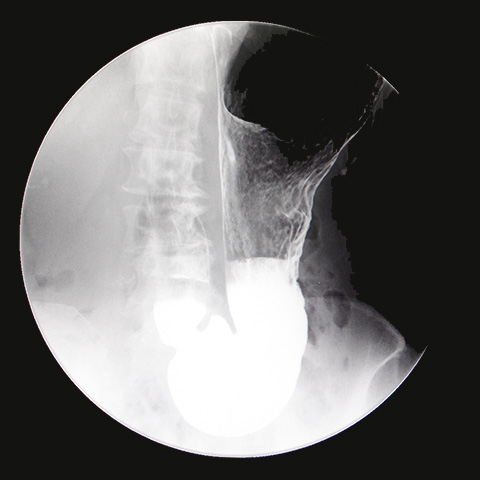

バリウムによるレントゲン検査です。

食道・胃や十二指腸などの形態や動き、粘膜の状態を観察して、がんや潰瘍などが無いか調べます。